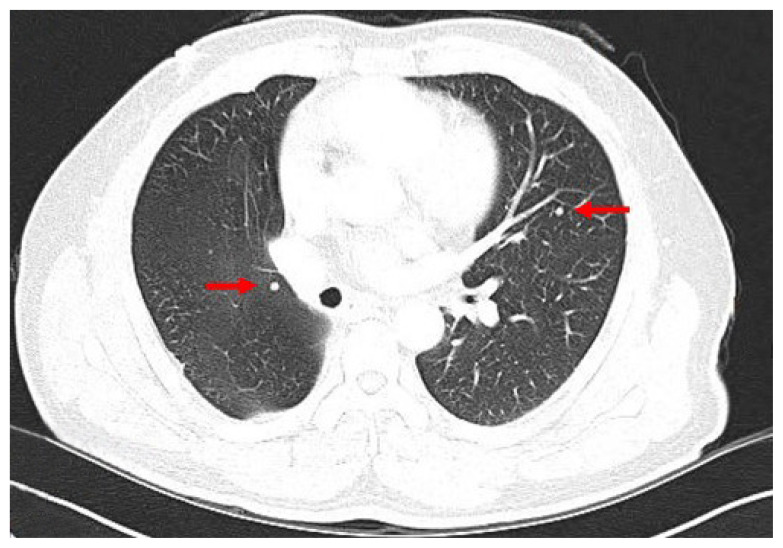

众所周知,分化良好的甲状腺癌(WDTC)会向骨和肺进行远处转移,而腹腔内和肠系膜转移则非常罕见。在此,我们报告了一例WDTC腹腔内肠系膜转移病例。一名 62 岁的男性因患滤泡性甲状腺癌接受了甲状腺叶切除术。一年后发现肺转移。患者同时接受了肺楔形切除术和甲状腺全切除术。11年后,患者血清甲状腺球蛋白水平升高。在检查中发现了肺部转移灶和肠系膜肿块。手术切除了肺部和肠系膜的两个病灶。肠系膜肿块经病理诊断为转移性 WDTC。

Distant metastases of well-differentiated thyroid cancers (WDTCs) to bone and lungs are well known, while intra-abdominal, mesenteric metastases are very rare. Herein, we report a case of intra-abdominal, mesenteric metastasis of WDTC. A 62-year-old man underwent thyroid lobectomy for follicular thyroid cancer. One year later, lung metastasis was observed. The patient simultaneously underwent lung wedge resection and complete thyroidectomy. Eleven years later, serum thyroglobulin level was elevated. On the work-up study, a metastatic lesion in the lungs and a mass in the mesentery were identified. Two lesions of the lung and mesentery were surgically resected. The mass in the mesentery was pathologically diagnosed as metastatic WDTC.